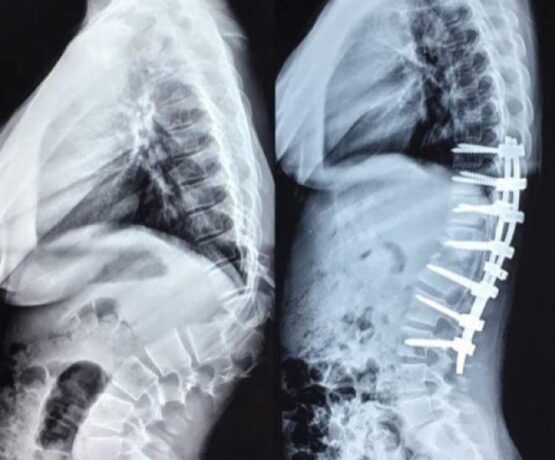

Correction of Congenital sharp angular kyphosis

Female pt 14 yrs, complaining from back pain due to congenital sharp angular kyphosis otherwise there wasn’t any neurological deficit Pre-op X-ray 3D Reconstruction Surgical…